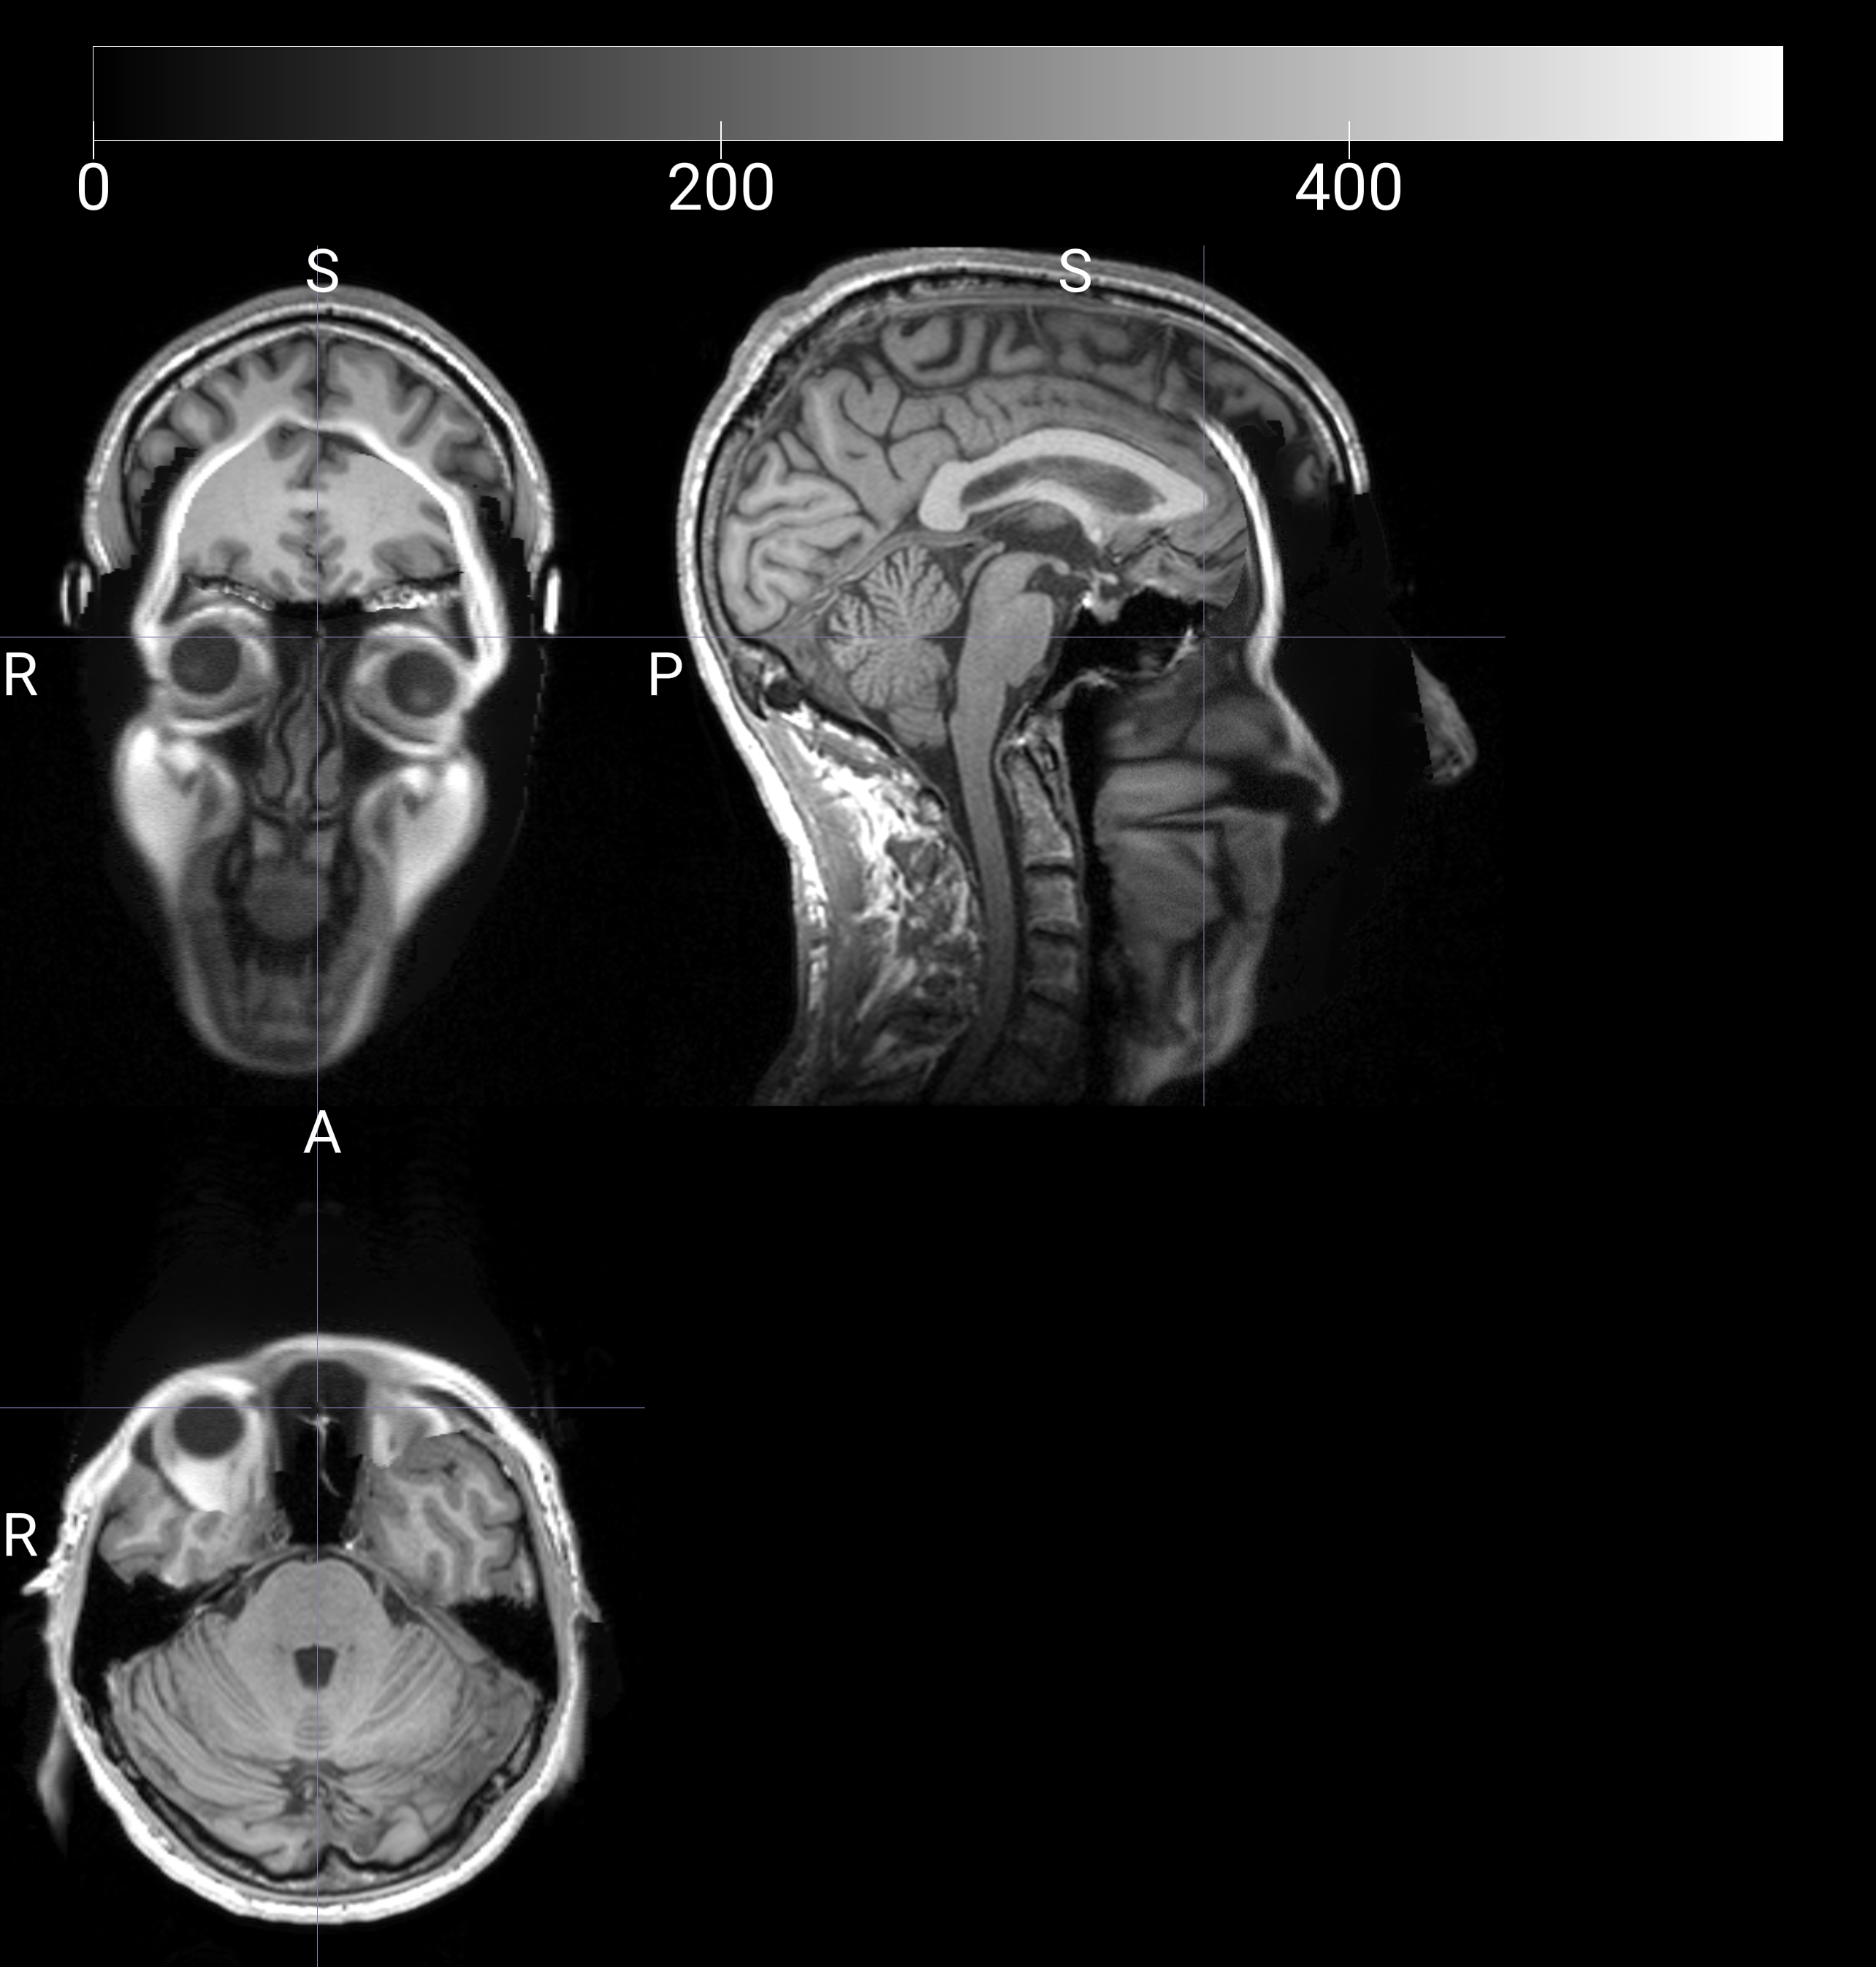

I've been using mri-reface on T1 images for my set of 33 participants. All worked well, except for the scans of 2 participants. The problem is that the new face is attached to the rest of the image in a way that it extends into and thus disrupts the brain. I attach an example image -- it's of my own brain/head, so I don't mind sharing it. (I think my head is too long in the y axis!) Do you have any recommendations for how I could fix this (e.g., are there settings I can adjust)? Or perhaps it requires some changes to the mri-reface package?

That doesn't look like a usual failure case where the registration just went bad. I suspect your input .nii file may have had a mismatched Sform/Qform. If that's the case, then the new version I uploaded today (0.3.3) would fix it.